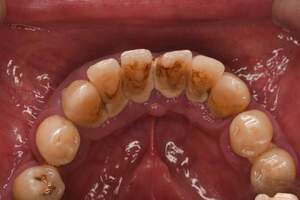

歯石除去

治療前1

治療後1

治療前2

治療後2

| 年齢 | 56歳・男性 |

|---|---|

| 主訴 | 主訴:歯石除去 治療部位:全顎 |

| 治療内容 | 初診検査・歯石除去 |

| 治療期間 | 60分 |

| 費用 | 合計約5,000円 初診検査約3,000〜4,000円 歯石除去約1,000円 (2024年4月現在) (歯の本数や検査内容で料金が変動します。) |

| リスク・副作用 | ・歯と歯の間に隙間ができるので、息が漏れ発音しにくいと感じることがあります。 ・歯ぐきの炎症がある場合は歯石除去中に出血を伴う可能性があります。 ・処置後に歯がしみることがあります。 ・歯ぐきの炎症が軽減すると歯ぐきが引き締まり、歯が長く見えることがあります。 |

| 治療方針 | 歯石除去・ブラッシング指導後SRP(歯ぐきの中に付着する歯石の除去) |

| 特記事項 | ・30年ぶりの歯科医院 ・毎食後の歯ブラシ習慣はあるが1分程度 |

| 担当者所見 | 全体の検査と歯石除去希望で来院されました。 特に下顎前歯部の歯と歯の間の歯石が、笑った時に見えてしまい気になるとのことで、初診検査後に歯石除去を行いました。 ブラッシング指導は歯間ブラシの入れ方と歯ブラシの動かし方をお伝えしました。 今後は治療と共に縁下歯石(歯ぐきの中に付着する歯石)の除去を行なっていく予定です。 |